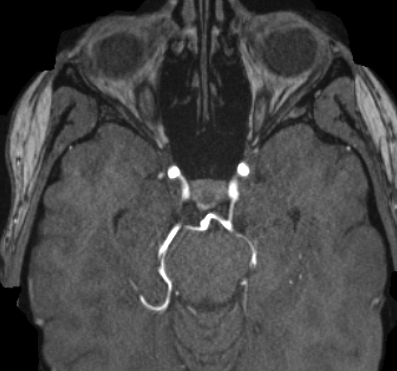

We hereby present a full synthetic model, able to mimic the various constituents of the cerebral vascular tree: the cerebral arteries, the bifurcations and the intracranial aneurysms. By building this model, our goal was to provide a substantial dataset of brain arteries which could be used by a 3D Convolutional Neural Network (CNN) to either segment or detect/recognize various vascular diseases (such as artery dissection/thrombosis) or even some portions of the cerebral vasculature, such as the bifurcations or aneurysms. In this study, we will particularly focus on Intra-Cranial Aneurysm (ICA) detection and segmentation. The cerebral aneurysms most often occur on a particular structure of the vascular tree named the Circle of Willis. Various studies have been conducted to detect and monitor the ICAs and those based on Deep Learning (DL) achieve the best performances. Specifically, in this work, we propose a full synthetic 3D model able to mimic the brain vasculature as acquired by Magnetic Resonance Angiography (MRA), and more particularly the Time Of Flight (TOF) principle. Among the various MRI modalities, the MRA-TOF allows to have a relatively good rendering of the blood vessels and is non-invasive (no contrast liquid injection). Our model has been designed to simultaneously mimic the arteries geometry, the ICA shape and the background noise. The geometry of the vascular tree is modeled thanks to an interpolation with 3D Spline functions, and the statistical properties of the background MRI noise is collected from MRA acquisitions and reproduced within the model. In this work, we thoroughly describe the synthetic vasculature model, we build up a neural network designed for ICA segmentation and detection, and finally, we carry out an in-depth evaluation of the performance gap gained thanks to the synthetic model data augmentation.